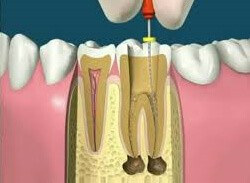

Possuimos em nossa clínica o mais alto nível tecnológico e de estrutura, afim de proporcionar um maior conforto e melhor atendimento para nossos pacientes.